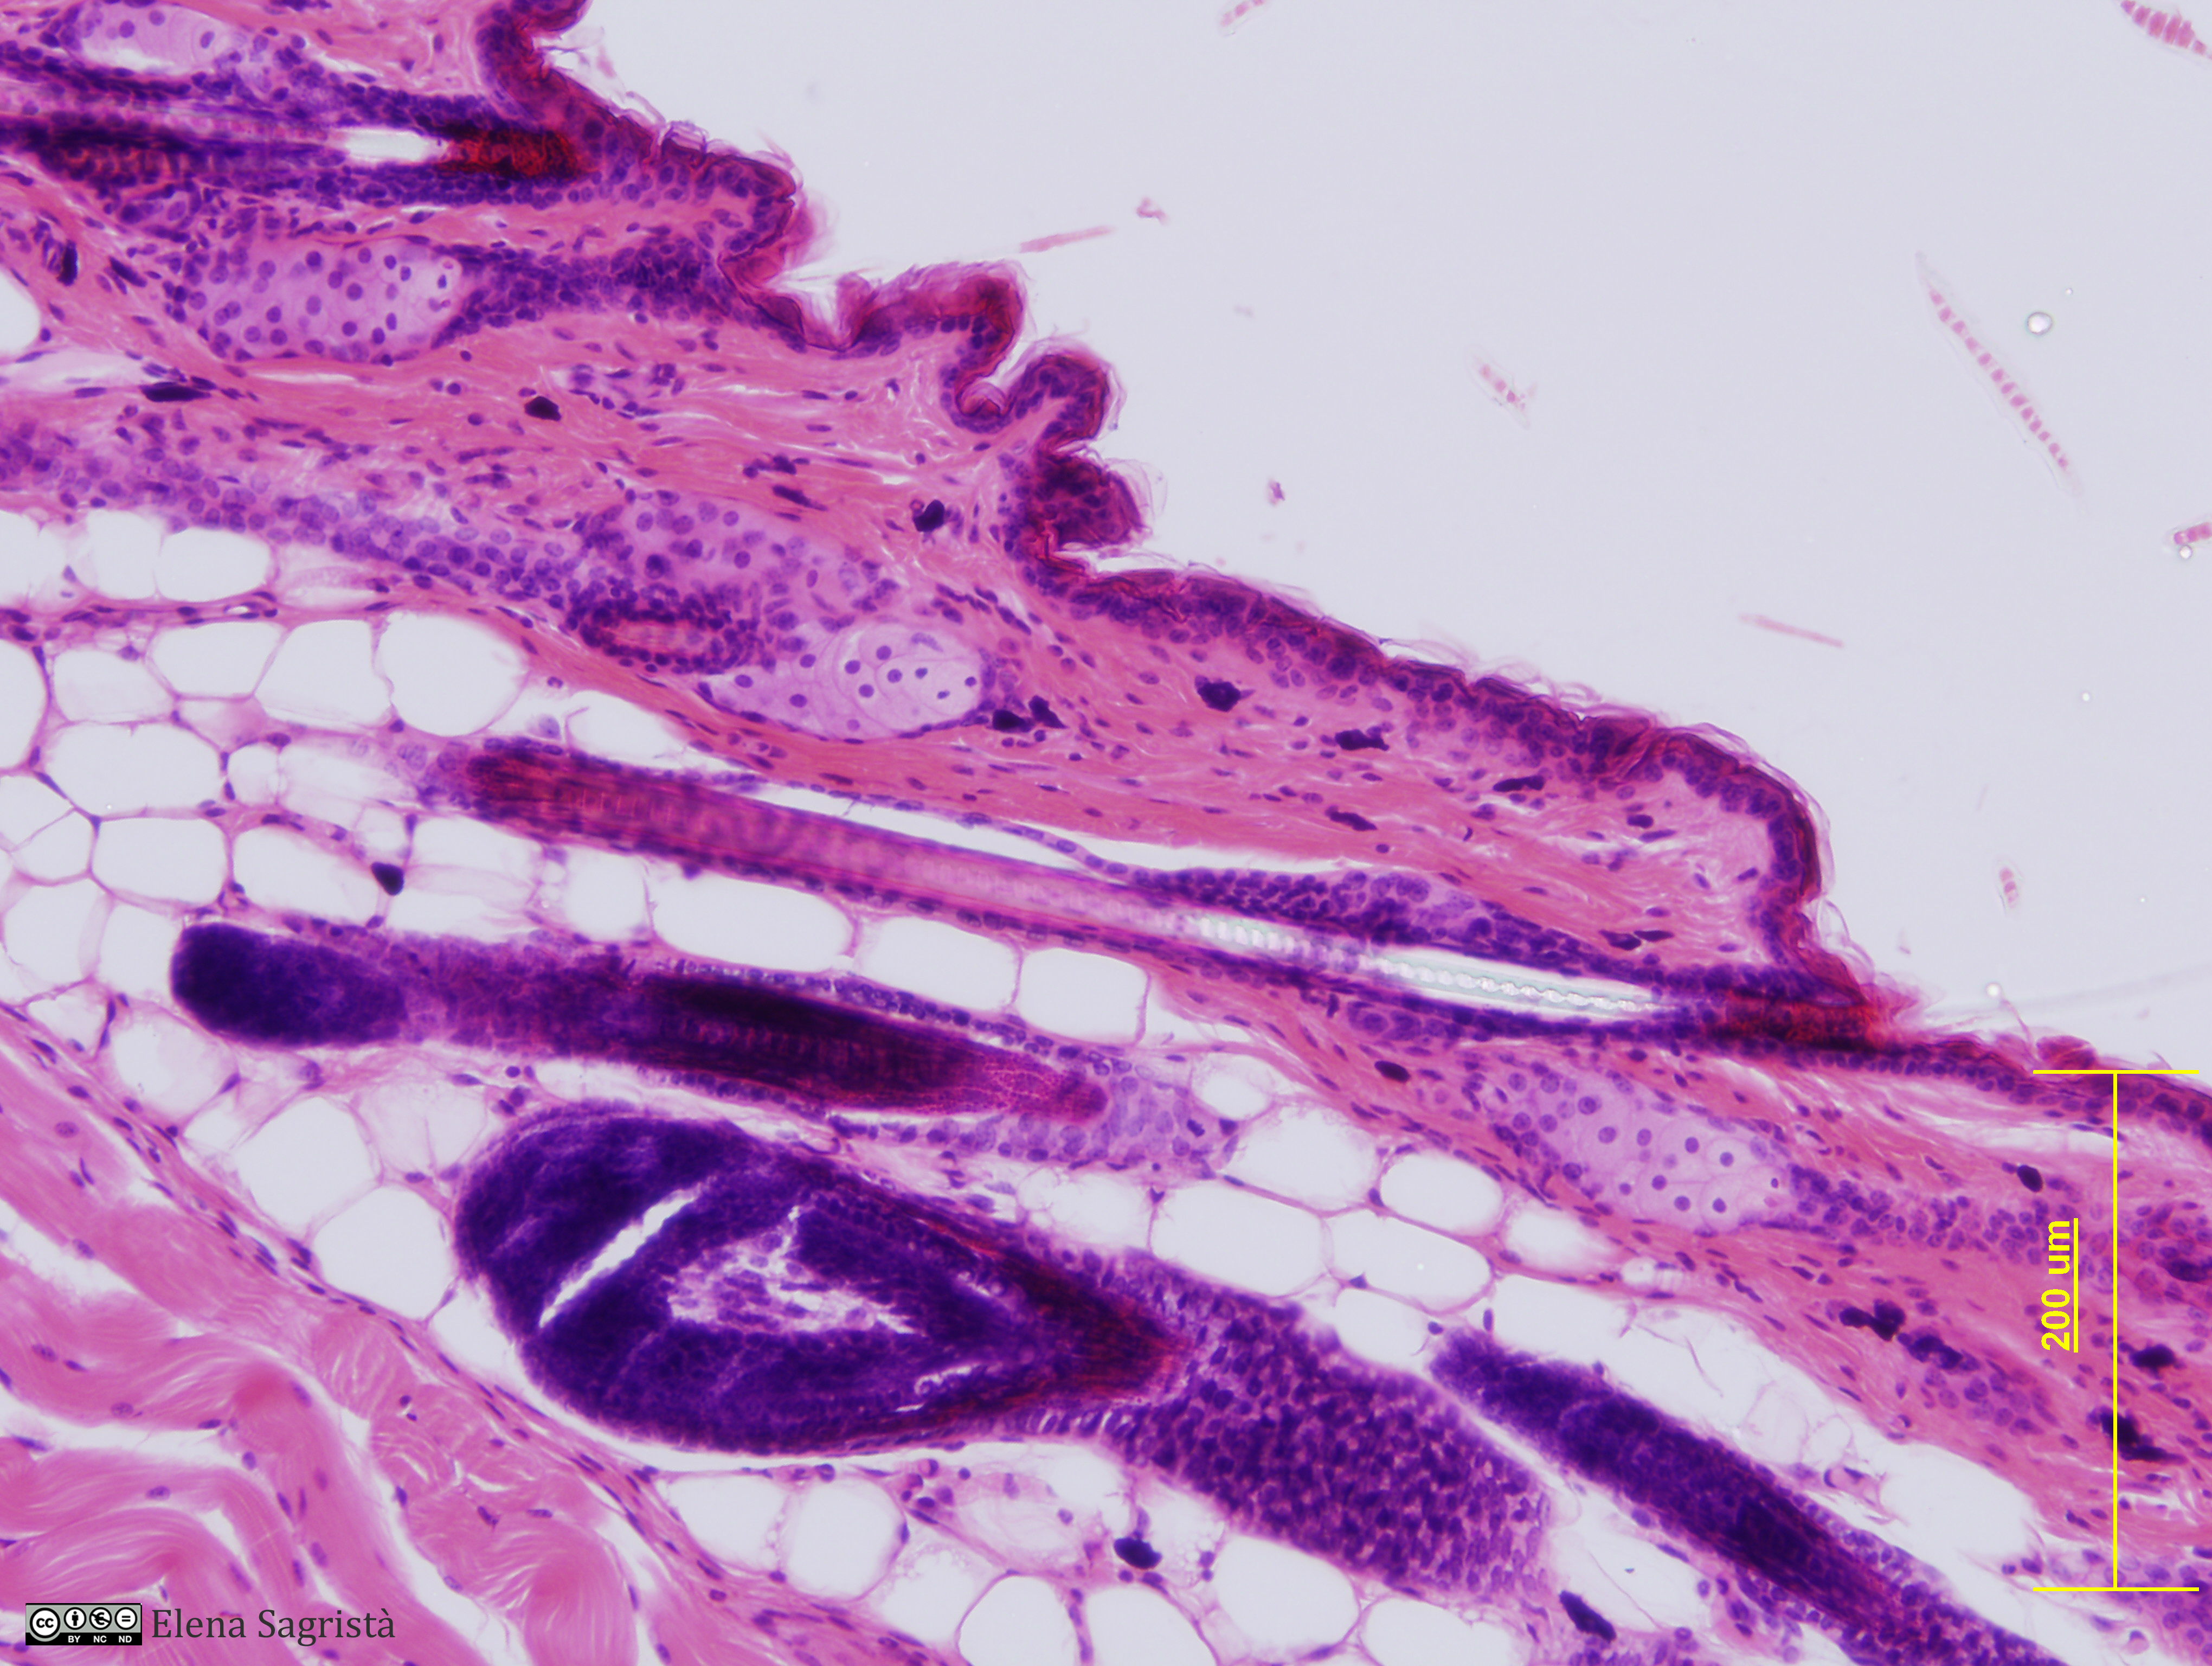

Histologia imatges: 11 Pell

Imatges de preparacions histològiques de Pell. Microscopia òptica.